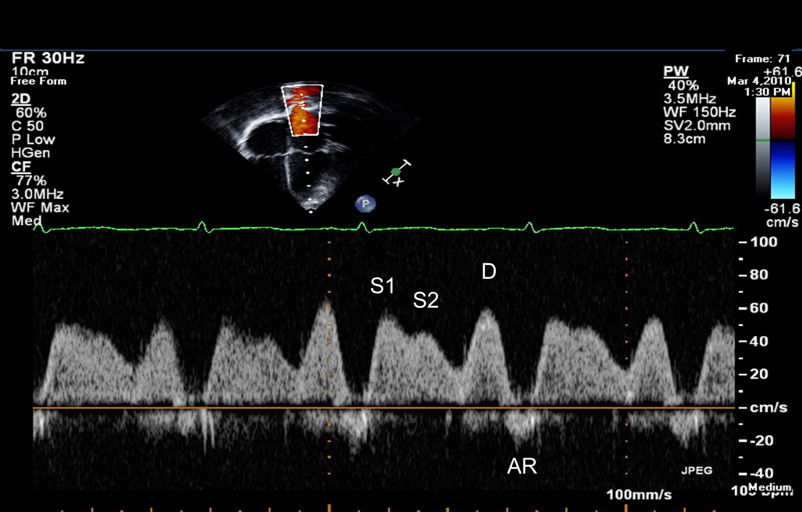

- Pulmonary venous flow: S velocity, D velocity, S/D ratio and AR duration. In diastolic dysfunction D> S and AR duration is longer

In severe diastolic dysfunction AR dur is prolonged, and the difference between ARdur (duration of A contraction in pulmonary veins) minus Adur (duration of contraction in mitral flow) is > + 30ms : ARdur – Adur > 30ms